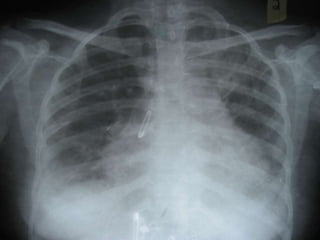

   New patches on chest X-Ray

   Consolidation with air bronchogram in the

apicoposterior segment of left upperlobe

   Minimal right pleural effusion with basal

atelectasis

   Moderate pericardial effusion